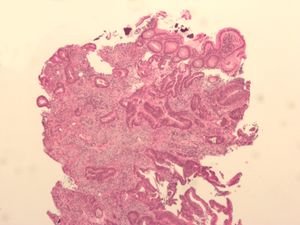

Micrograph of a tubular adenoma, a type of colonic polyp and a precursor of colorectal cancer.

Micrograph of an invasive adenocarcinoma (the most common type of colorectal cancer). The cancerous cells are seen in the center and at the bottom right of the image (blue). Near normal colon-lining cells are seen at the top right of the image.

Histopathologic image of colonic carcinoid stained by hematoxylin and eosin.